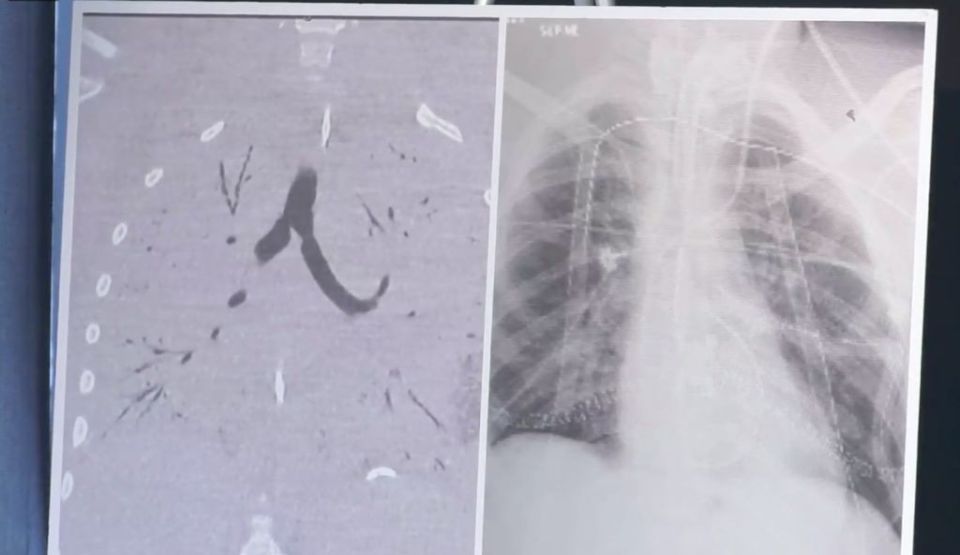

Un adolescent a murit pe 6 noiembrie într-un spital din Bruxelles în urma complicaţiilor pulmonare, doctorii care s-au ocupat de cazul său suspectând că problemele medicale ale victimei au fost cauzate de folosirea ţigaretei electronice.

Adolescentul ar fi primit drept cadou o ţigaretă electronică şi a folosit ulei de CBD (cannabidiol, o substanţă prezentă şi în canabis care nu are efecte psihoactive). Doctorii suspectează că folosirea acestei substanţe a condus la o deteriorare rapidă la nivel pulmonar, potrivit Mediafax.